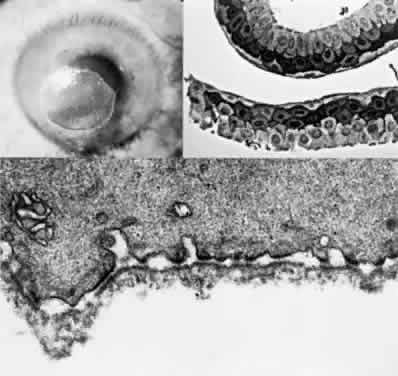

This disease, also known as Gunther's disease, is an autosomal-recessive disorder. It is caused by a deficiency of uroporphyrinogen III synthase activity, resulting in an overproduction of porphyrins (type I) for which the body has no use. Different molecular defects have been detected.67 The clinical signs include hydroa aestivate (a vesicular or bullous eruption of the face, backs of the hands, and other exposed areas of the body), erythrodontia (brownish discoloration of the teeth), hypertrichosis, and splenomegaly.68 Neurologic symptoms, hypertension, and abdominal colic are not found.

Ocular Findings. Ocular manifestations of this disorder include cicatricial ectropion, loss of eyelashes and eyebrows, bilateral exophthalmos, optic atrophy, retinal hemorrhages, and chorioretinitis.69–71 Conjunctivitis may result in marked scarring and adhesion of the conjunctiva to the sclera. Decreased corneal sensitivity, corneal scarring and vascularization, corneal perforation at the limbus, and scleromalacia may occur. Histopathology of tissue from a patient who underwent a penetrating keratoplasty and conjunctival resection revealed a thickened basement membrane of the vessels within the conjunctival and corneal stroma. Microfibrillar material was seen in the extracellular spaces of the conjunctival stroma. Inflammatory cells were noted in the corneal stroma, and there was a loss of keratocytes. Descemet's membrane lacked the normal fetal and postnatal banding and the endothelium was severely damaged.72 The changes in the vessels and conjunctival stroma were similar to those described in the skin of porphyria patients exposed to ultraviolet light.